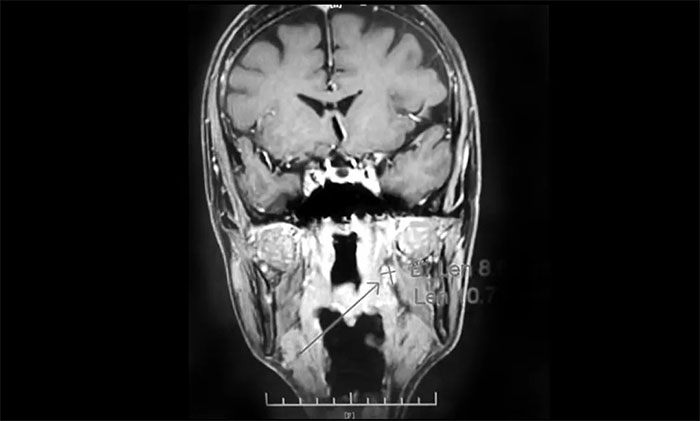

經(jīng)MDT多學(xué)科會診評估,制定以放療為主的同步放化療方案。治療后復(fù)查MRI,患者左側(cè)鼻咽部實(shí)性占位較前治療明顯減小;原左側(cè)下頜腺區(qū)、咽旁腫大淋巴結(jié)已基本吸收好轉(zhuǎn),左頸部腫大淋巴結(jié)較前明顯縮小。

▲ 放療后復(fù)查MRI,腫瘤占位較前明顯減小